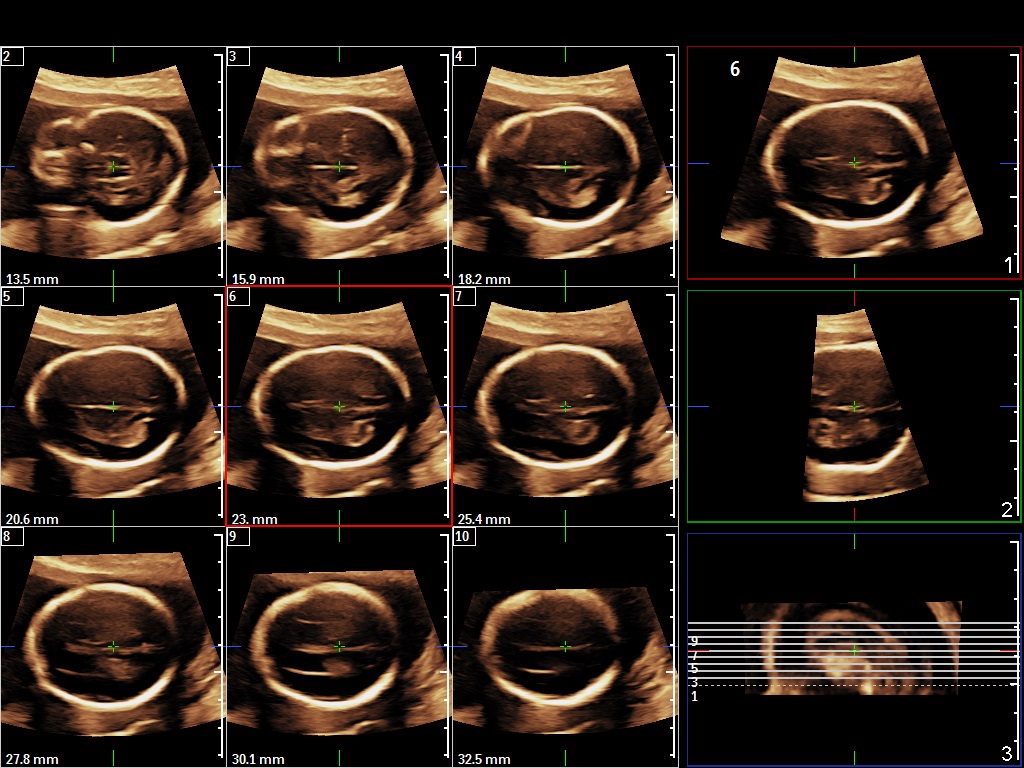

In the second trimester choroid plexus cysts are found in 1–3% of normal fetuses and in 30–50% of trisomy 18 fetuses (Dagklis T. et al., 2008).

The presence of choroid plexus cysts increases the risk for aneuploidy, mainly trisomy 18. In the majority of cases, the final risk will remain small, but will increase as maternal age increases (Chitty L. et al., 1998).

In cases of isolated choroid plexus cysts and low a priory patient’s risk for trisomy 18 we do not recommend invasive testing for fetal karyotyping (Geary M., et al., 1997).